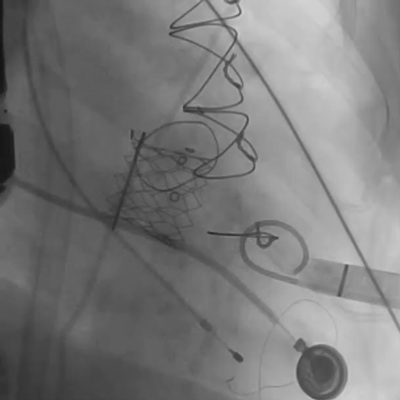

经过手术团队充分讨论病例资料,模拟在首次手术生物瓣环与第二次手术瓣膜内植入定位更精准的佰仁Renato®球扩式瓣中瓣,以有效治疗二尖瓣自膨式介入瓣毁损。手术按照术前讨论方案进行,过程顺利,成功植入27号Renato®球扩瓣,瓣膜植入位置理想,启闭功能表现出色。左室造影及经食道超声观察无明显瓣中及瓣周反流,平均跨瓣压差降至8.0mmHg。

球扩瓣释放

瓣中瓣植入后

无明显瓣中及瓣周反流